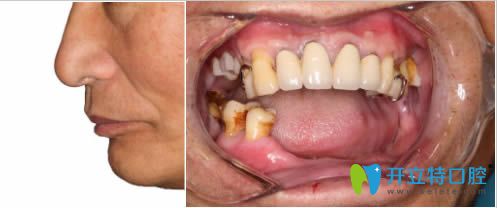

【本院隱適美齙牙矯正后臉型變化對(duì)比圖】:

洛陽(yáng)拜博隱適美齙牙矯正后臉型變化對(duì)比圖